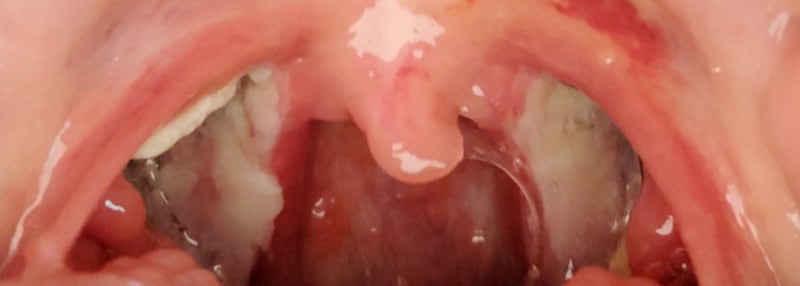

<5일차> (병원진료 예약일)

5일째 아침! 눈을 뜨니 어제 아침보다는 다시 좋아졌어 ㅋㅋ 신기해~ 뽀로로카스텔라를 우유에 타서 먹고 오빠가 만들어놓고 간단 백질쉐이크도 꾸물꾸물..목이 아파서 다 못먹고… 재채기가 나서 죽을뻔했어…목 수술을 다시 할 뻔했다. ㅎㅎㅎㅎㅎㅎ

약을 먹고 출근을 했는데 약이 너무 강해서 그런 정신이 없어서 조금 멍한 상태에서 계속 구역질이 났어 ㅜ 그리고 퇴원 후 진료 예약한 날이니까 검사를 받았더니 지금은 잘 나았다고 일주일 동안 약을 먹고 죽을 먹으라고 했다.ㅋㅋㅋㅋ 질린 죽^^ 참고로 살 빼지 않고 유지하는 중..살이 좀 빠지면 좋겠다.그리고 점심은 먹지 않았다.약 먹기 싫어서 안 먹었어.